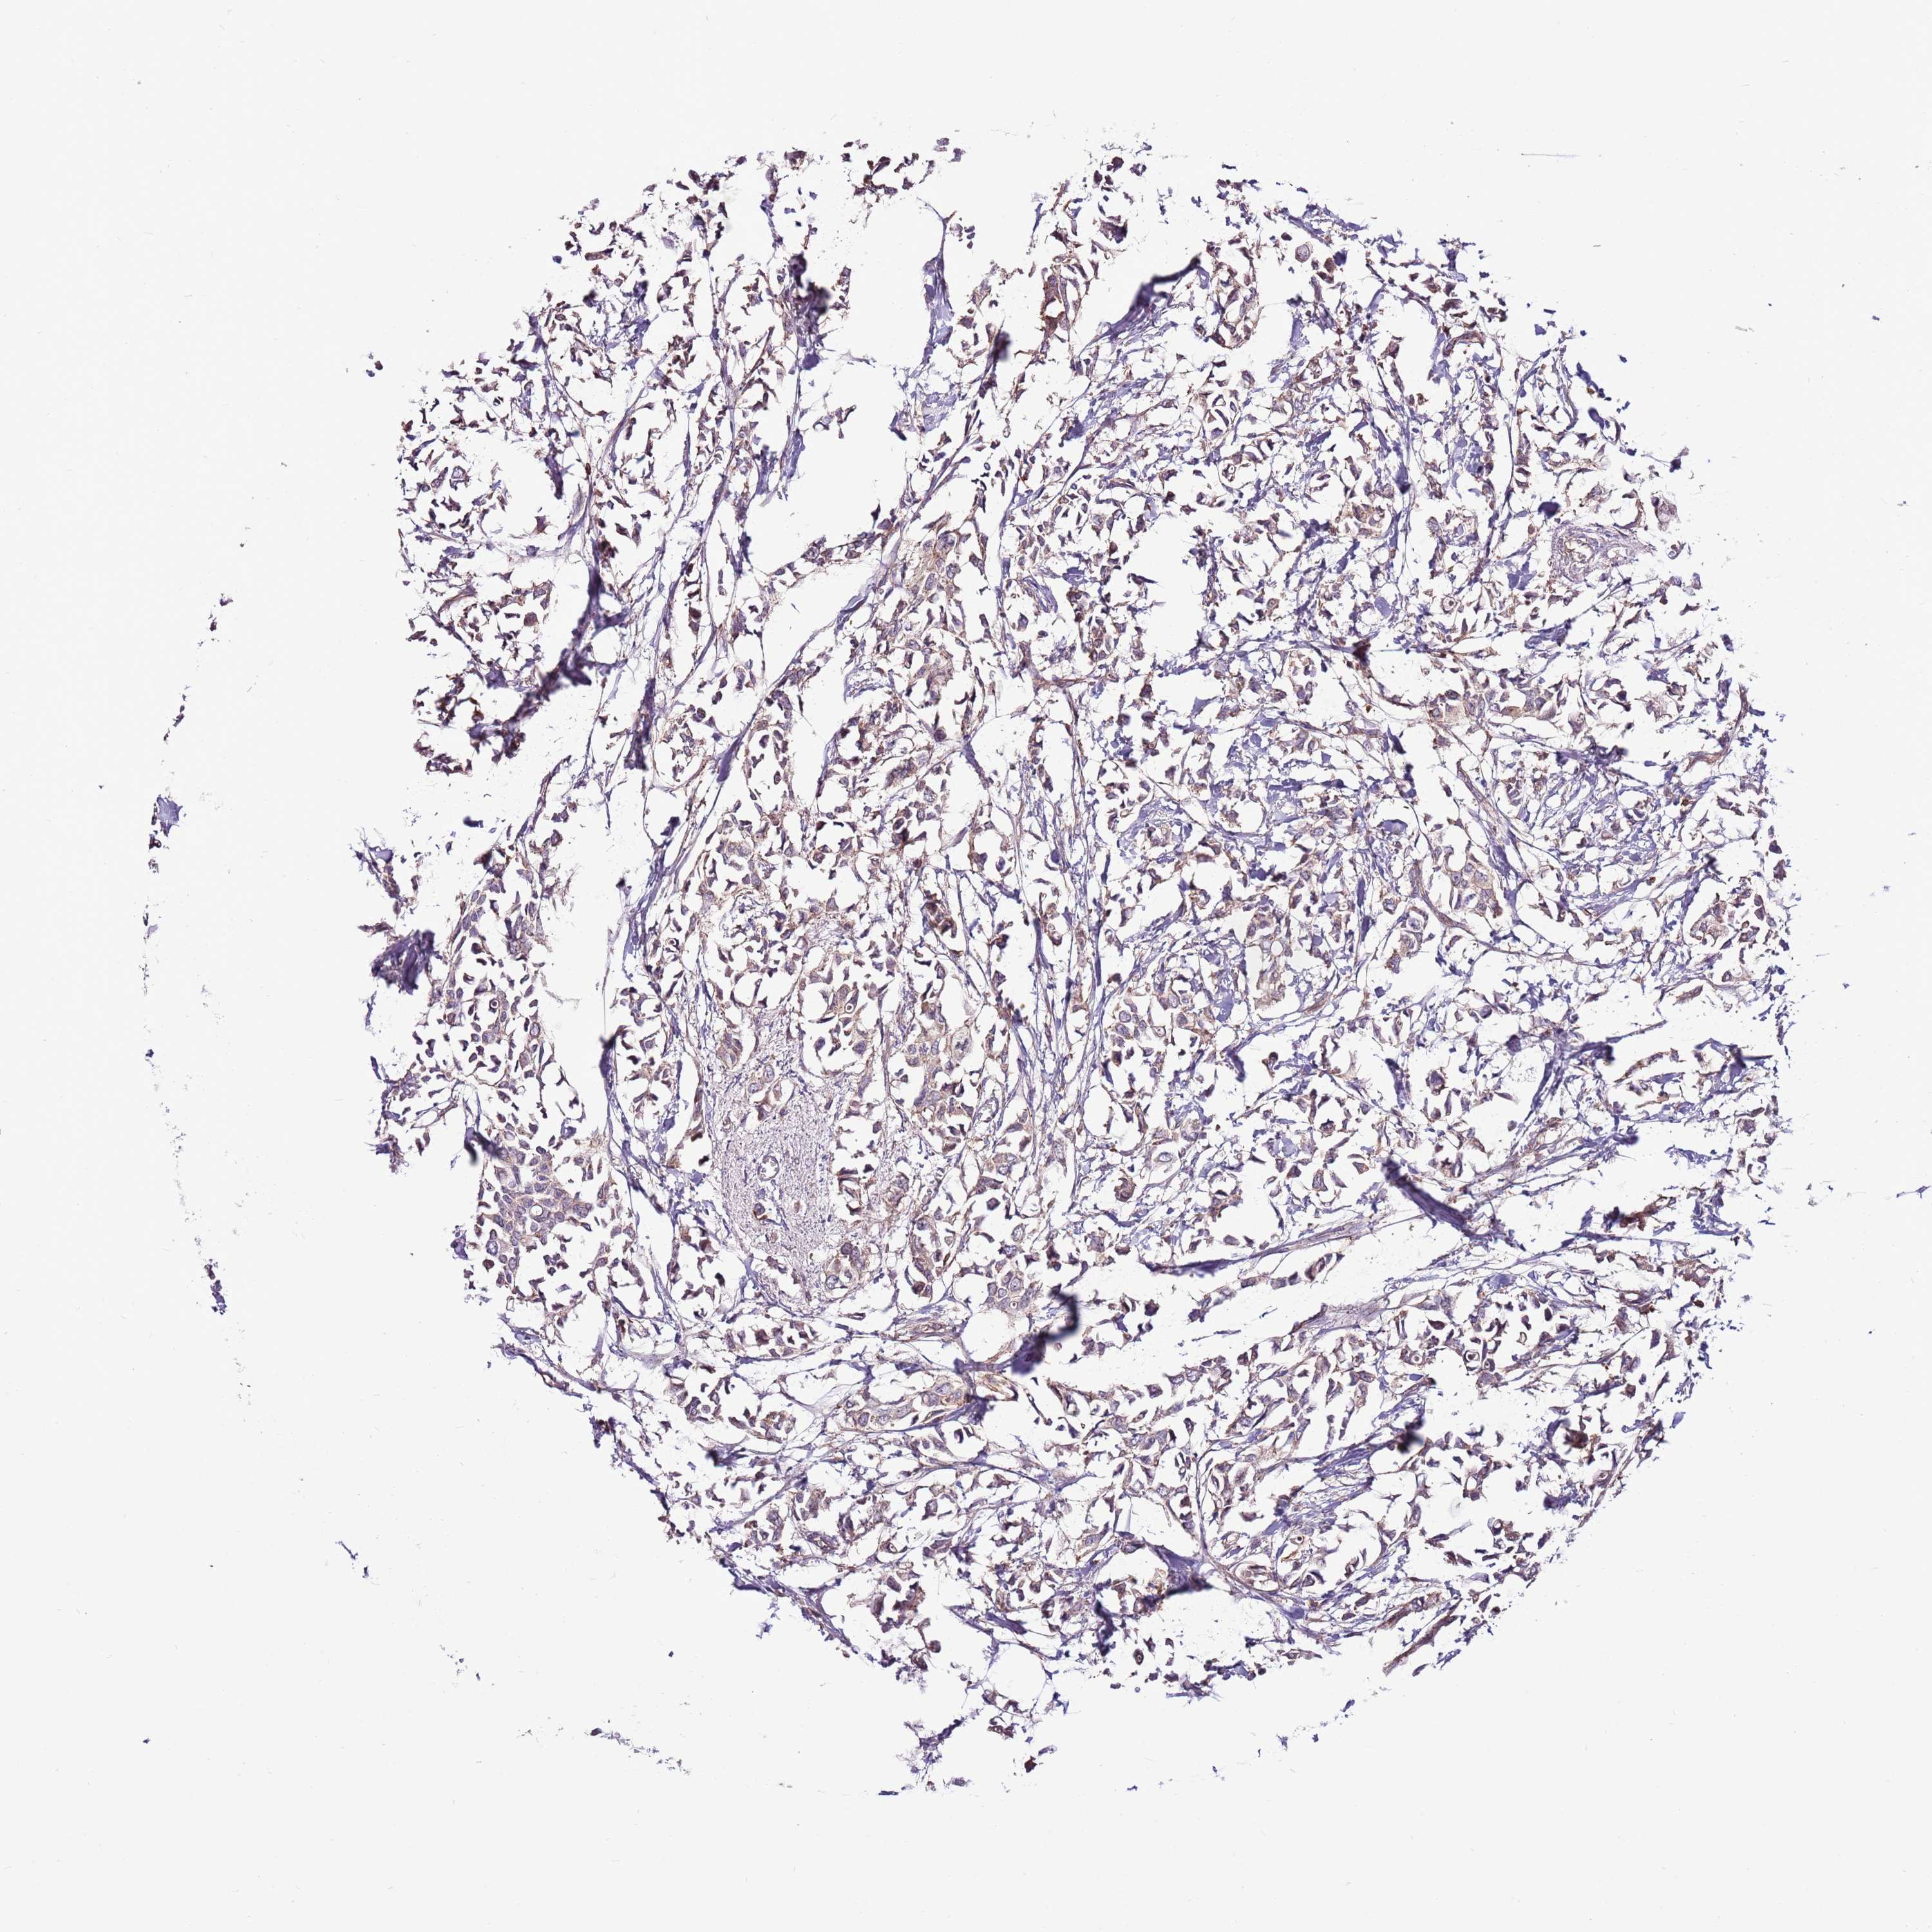

BRCA TCGA BRCA VALIDATION PROTEIN EXPRESSION

ANTIBODIES

AND

VALIDATION